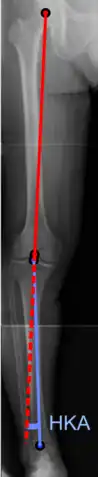

On projectional radiography, the degree of varus or valgus deformity can be quantified by the hip-knee-ankle angle,[8] which is an angle between the femoral mechanical axis and the center of the ankle joint.[9] It is normally between 1.0° and 1.5° of varus in adults.[10] Normal ranges are different in children.[11]

Hip-knee-ankle angle.